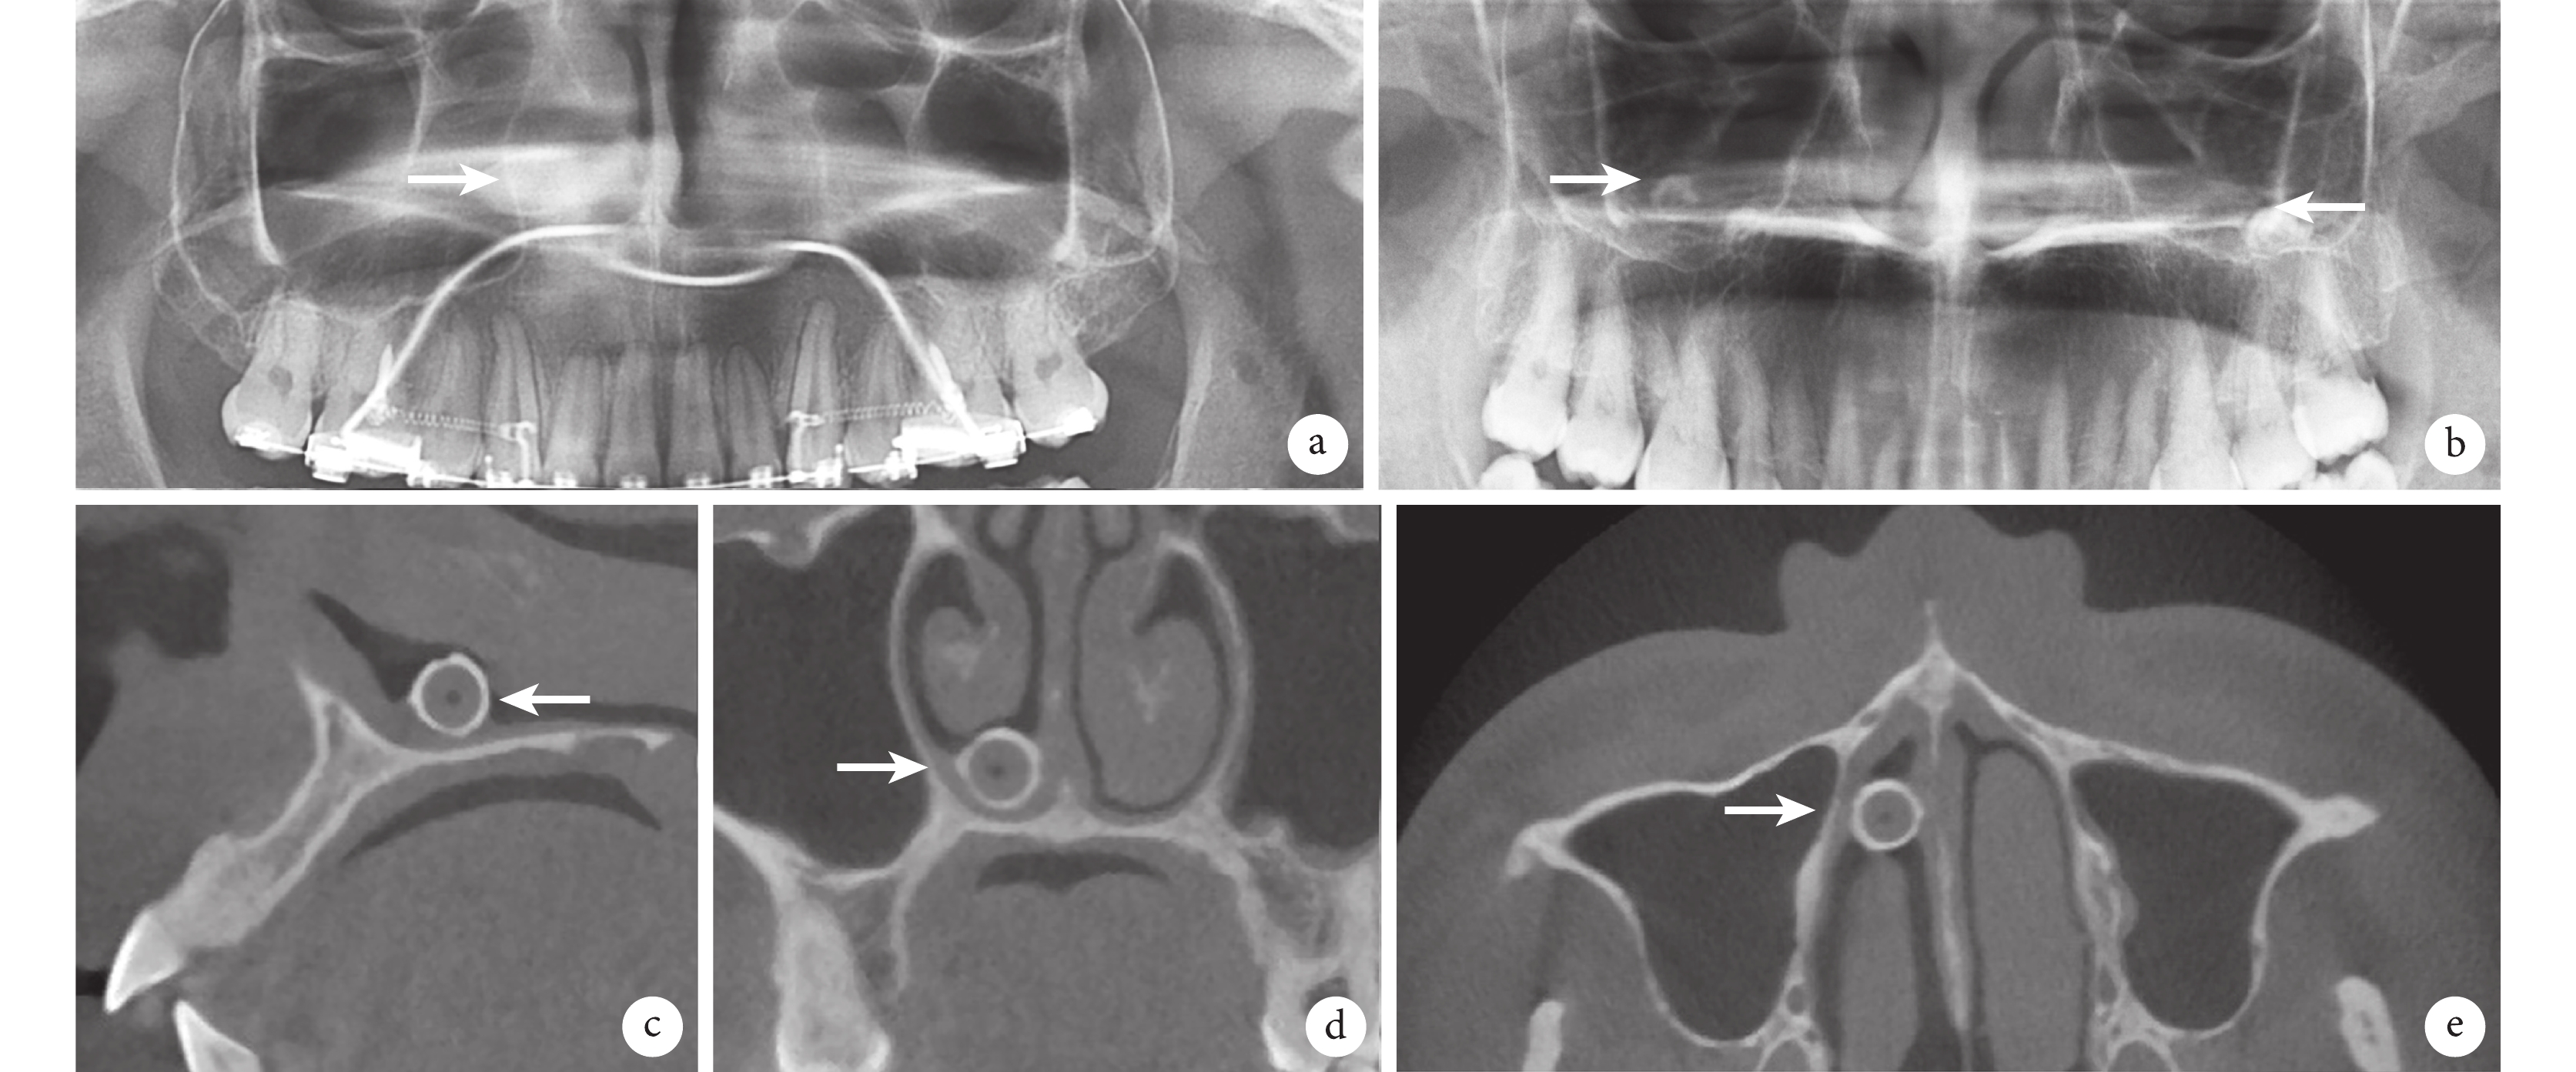

由于病變位置深在,多結構重疊,全景片中難以觀察到準確的鼻石竇石結構影像,病變結構不清,圖像變形(圖 5a、5b),常需要借助頭顱后前片、口腔頜面部錐形束 CT(cone beam computer tomography,CBCT)等手段確診(圖 5c~5e)。

a. 鼻石患者全景片,鼻石位于右側鼻腔(白箭);b. 雙側上頜竇竇石(白箭)全景片;c~e. 分別為鼻石 CBCT 矢狀位截圖、冠狀位截圖和軸位截圖,鼻石位于右側鼻腔(白箭)